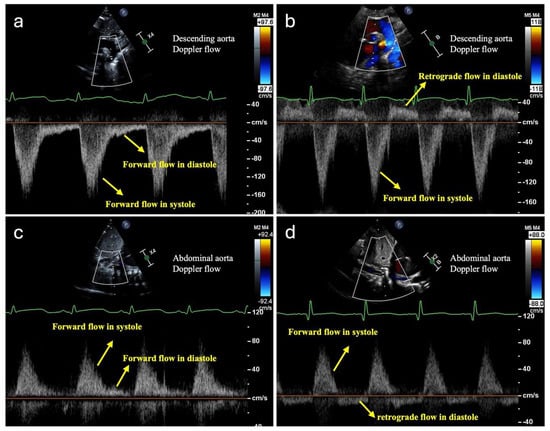

3.1. Monitoring Systemic Hypoperfusion and Hypoxia

3.2. Monitoring Pulmonary Overcirculation